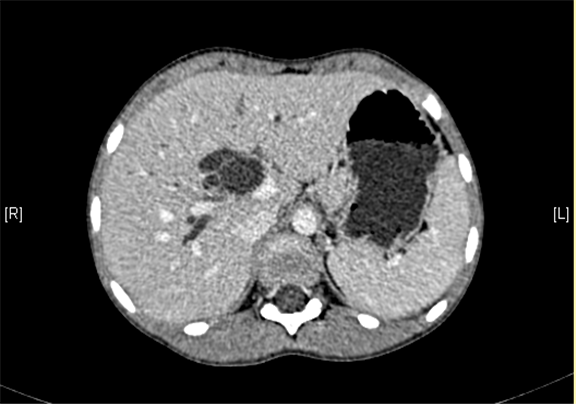

上腹部增强CT:肝内外胆管扩张,考虑胆管囊肿(以左右肝管、肝总管及胆总管扩张明显)可能性大。

术前CT检查:

动脉期